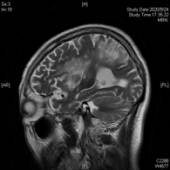

患者老李由于突发脑梗死,一觉醒来竟然听不懂别人的一句话,也说不出一个字,就连简单的“a”、“o”、“e”都说不出来。这对于作为教师的老李来说,无疑是晴天霹雳,当头一棒。经头颅核磁检查显示:老李的左侧大脑大面积脑梗死。老李是右利手,他的优势半球为大脑左半球,也就是支配我们语言的脑区。然而,不幸地是这个区域脑区几乎没有一丁点地儿在这场灾难中幸存,自发语极少,听觉理解、文字理解严重障碍,命名、复数、读词不能,听、说、读、写所有语言模式受到严重损害,诊断为完全性失语伴有言语失用。于是在他人的眼里,他似乎变得“又聋又哑”,既听不明白别人说什么也说不出来一句话,像是他的世界屏蔽了信号,接收不到任何语言的输入,也输出不了任何语言符号。这可急坏了老李的老伴,这以后可怎么办呀?